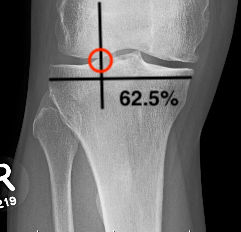

C. Fujisawa point / Weight bearing line method

Fujisawa point

- 62.5% from medial edge medial tibial plateau

- just lateral to lateral tibial spine

Line A: Center femoral head to Fujisawa point to level ankle

Line B: Center ankle joint to Fujisawa point

The angle between these lines is the angle of the desired correction